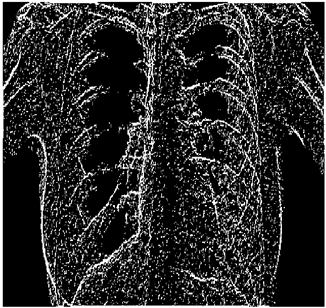

Table 5. X-ray Images.

X-ray 1X-ray 2X-ray 3X-ray 4X-ray 5

Mathematics 10 02421 i004 Mathematics 10 02421 i005 Mathematics 10 02421 i006 Mathematics 10 02421 i007 Mathematics 10 02421 i008

For the purpose of simulation, we consider two sets of images: (1) three images from MATLAB repository (Table 4) and (2) five X-ray images available online (Table 5).